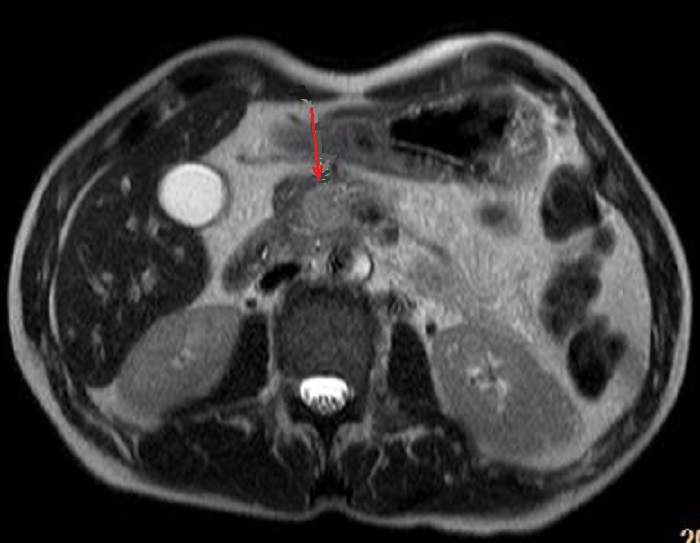

En cas ponderation sur T1

avec de contrast intraveineuse le tumeur apparaitre

hypersignal a 3 minute apres injection de contrast . Image radiologique IRM ponderee sur T1 C+ |

Meme cas en coupe coupe

frontale ( fleche rouge ) |